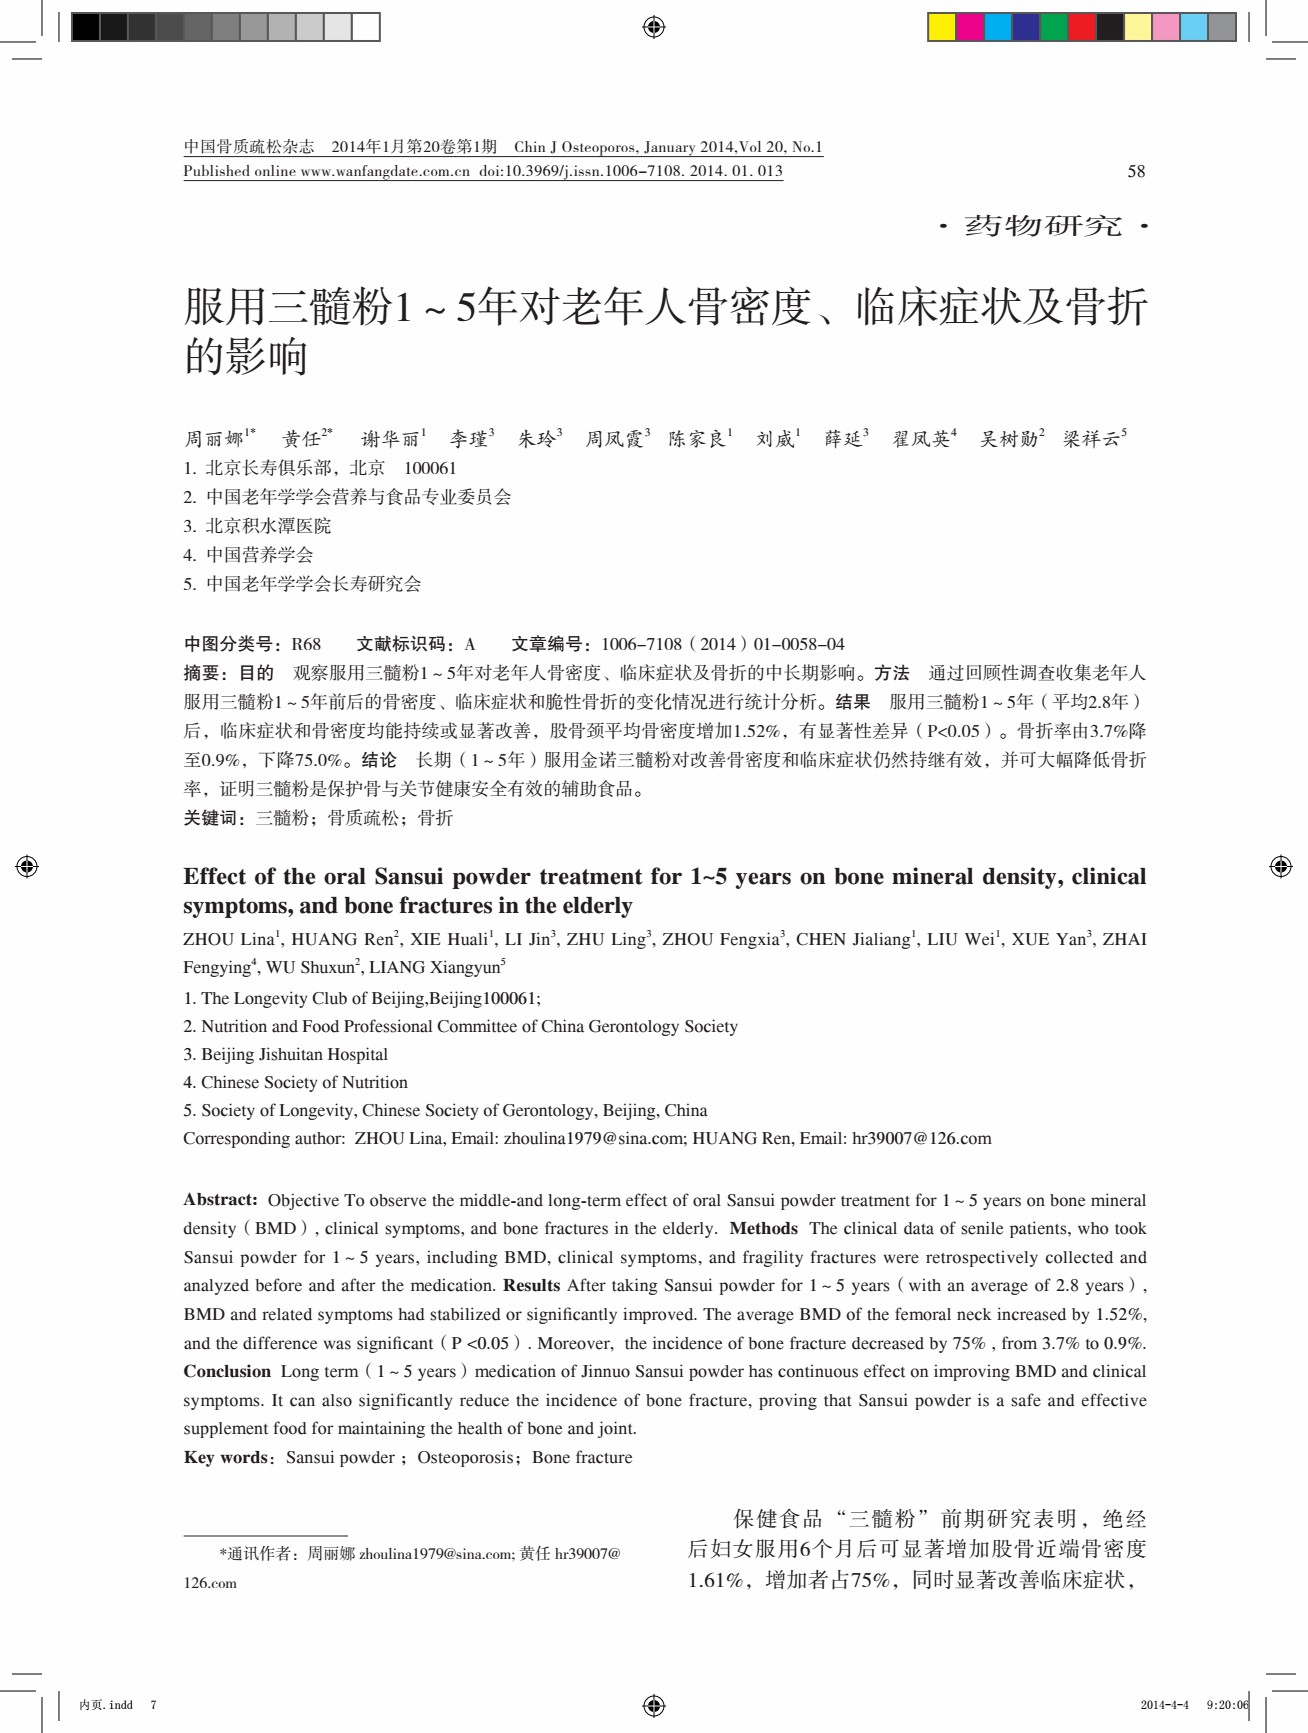

“三髓粉”对绝经后妇女骨密度及骨症状改善的研究

服用三髓粉1〜5年对老年人骨密度、临床症状及骨折的影响